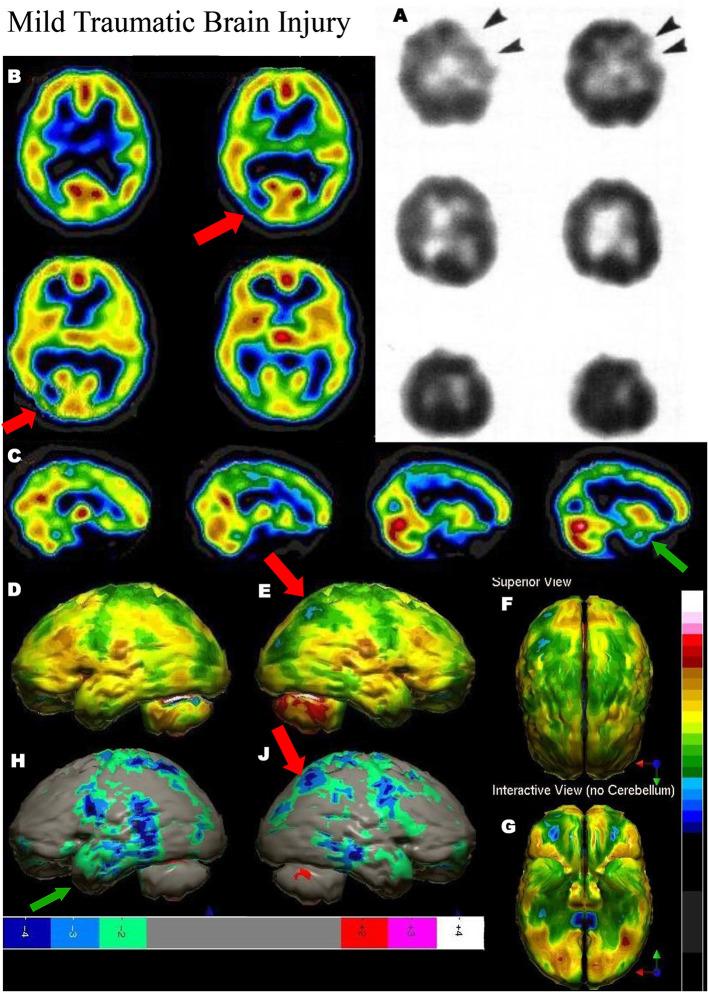

Brain perfusion single photon emission computed tomography (SPECT) scans were initially developed in 1970's. A key radiopharmaceutical, hexamethylpropyleneamine oxime (HMPAO), was originally approved in 1988, but was unstable. As a result, the quality of SPECT images varied greatly based on technique until 1993, when a method of stabilizing HMPAO was developed. In addition, most SPECT perfusion studies pre-1996 were performed on single-head gamma cameras. In 1996, the Therapeutics and Technology Assessment Subcommittee of the American Academy of Neurology (TTASAAN) issued a report regarding the use of SPECT in the evaluation of neurological disorders. Although the TTASAAN report was published in January 1996, it was approved for publication in October 1994. Consequently, the reported brain SPECT studies relied upon to derive the conclusions of the TTASAAN report largely pre-date the introduction of stabilized HMPAO. While only 12% of the studies on traumatic brain injury (TBI) in the TTASAAN report utilized stable tracers and multi-head cameras, 69 subsequent studies with more than 23,000 subjects describe the utility of perfusion SPECT scans in the evaluation of TBI. Similarly, dementia SPECT imaging has improved. Modern SPECT utilizing multi-headed gamma cameras and quantitative analysis has a sensitivity of 86% and a specificity of 89% for the diagnosis of mild to moderate Alzheimer's disease-comparable to fluorodeoxyglucose positron emission tomography. Advances also have occurred in seizure neuroimaging. Lastly, developments in SPECT imaging of neurotoxicity and neuropsychiatric disorders have been striking. At the 25-year anniversary of the publication of the TTASAAN report, it is time to re-examine the utility of perfusion SPECT brain imaging. Herein, we review studies cited by the TTASAAN report vs. current brain SPECT imaging research literature for the major indications addressed in the report, as well as for emerging indications. In Part II, we elaborate technical aspects of SPECT neuroimaging and discuss scan interpretation for the clinician.

脑灌注单光子发射计算机断层扫描(SPECT)最初是在20世纪70年代开发的。一种关键的放射性药物,六甲基丙烯胺肟(HMPAO),最初于1988年获批,但不稳定。因此,直到1993年开发出一种稳定HMPAO的方法之前,SPECT图像的质量因技术不同而有很大差异。此外,1996年以前的大多数SPECT灌注研究是在单头伽马相机上进行的。1996年,美国神经病学学会治疗与技术评估小组委员会(TTASAAN)发布了一份关于SPECT在神经系统疾病评估中应用的报告。尽管TTASAAN报告于1996年1月发表,但它于1994年10月被批准发表。因此,TTASAAN报告中用于得出结论的脑SPECT研究大多早于稳定HMPAO的引入时间。虽然TTASAAN报告中关于创伤性脑损伤(TBI)的研究只有12%使用了稳定示踪剂和多头相机,但随后有69项研究涉及超过23000名受试者,描述了灌注SPECT扫描在TBI评估中的效用。同样,痴呆症的SPECT成像也有所改进。利用多头伽马相机和定量分析的现代SPECT对轻度至中度阿尔茨海默病诊断的敏感性为86%,特异性为89%,与氟脱氧葡萄糖正电子发射断层扫描相当。癫痫神经成像也取得了进展。最后,神经毒性和神经精神疾病的SPECT成像发展显著。在TTASAAN报告发表25周年之际,是时候重新审视灌注SPECT脑成像的效用了。在此,我们回顾了TTASAAN报告引用的研究与当前脑SPECT成像研究文献,涉及该报告中讨论的主要适应症以及新出现的适应症。在第二部分中,我们详细阐述了SPECT神经成像的技术方面,并讨论了临床医生对扫描结果的解读。